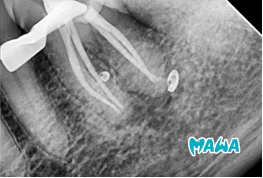

4️⃣ Obturación del Conducto

La obturación se realizó mediante técnica termoplastificada combinada con cemento sellador AH-PLUS.

Esta combinación permite un excelente sellado tridimensional, adaptándose perfectamente a las irregularidades del conducto y garantizando un cierre hermético que previene la reinfección futura.